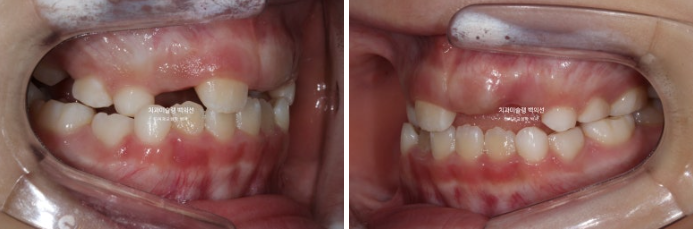

2022년 8월 내원한 어린이 입니다.

앞니 반대교합과 비대칭 치료를 위해 오셨습니다.

앞니 뿐 아니라 송곳니, 일부 어금니까지 거꾸로 물리는 상황입니다.

앞니 반대교합은 프리올소와 같은 장치로 간단하게 넘겨줄 수 있지만 더 큰 문제는 비대칭입니다.

아래앞니와 함께 아래턱이 우측으로 돌아가 있습니다.

골격분석 결과 페이스마스크와 같이 적극적인 주걱턱 치료는 불필요하고 가성주걱턱일 가능성이 높아 간단하게 반대교합 부터 넘기기로 합니다.